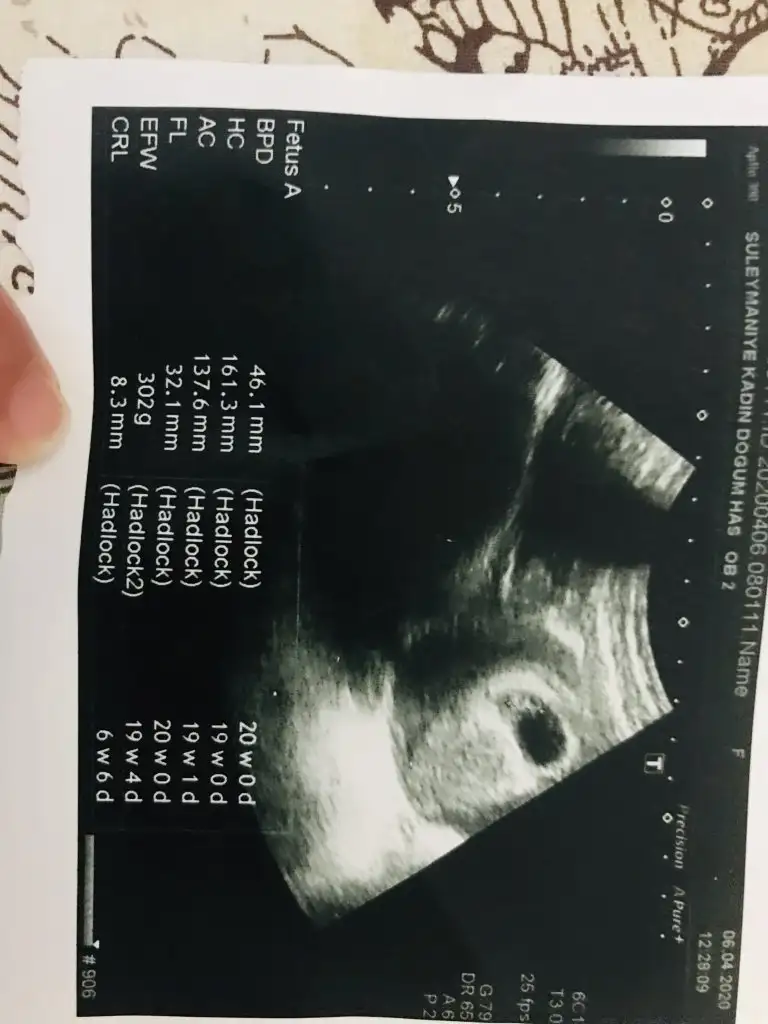

eklediğim fotolar vajinal ultrasondan ve burada 5+4 haftalık:)

Ben kese konumunu pek tuttugunu sanmıyorum ben nub tahmini yapıyorum 11 yada 12 hafta olmalı kesede yolk saç nerde ise yani sag tarafta hafif kabarık beyaz parlak alan sagda tabi siz vajinal bakıldıgı için asıl solda olmuş oluyor karından bakılınca asıl sol olmuş olacaktı ve erkek 😊

merhaba tekrar siz benim bebeğimin kese konumuna göre erkek olur gibi yorumu yapmıştınız,

Bugün 12.hafta kontrolüne gittim ikili tarama için doktor cinsiyetine %75 erkek gibi dedi tabi yanılma payı vardır yoktur bilemicem başta sağlıklı olmasını diliyorum rabbimden:)

Ben şimdilik tahmininizin kısmen tuttuğunu söylemek için yazdım özellikle.. ultrason fotosunu da ekliyim 12.hafta içinde nub teoremiyle tahminlerinizi alıyım böylece birlikte teyit etmiş olalım şimdiden teşekkür ediyorum :)